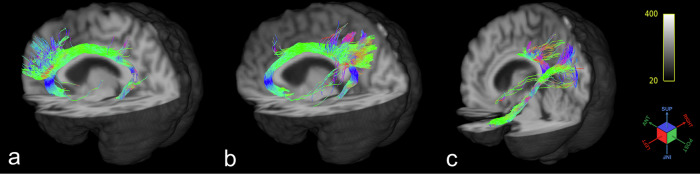

Methods: Multi-shell high angular resolution diffusion imaging-HARDI image datasets from the "Alzheimer's Disease Neuroimaging Initiative"-ADNI repository of 10 AD, 18 MCI, and 21 cognitive normal (CN) subjects were used to reconstruct three subdivisions of the cingulum bundle, using a probabilistic approach, combined with measurements of diffusion tensor and neurite orientation dispersion and density imaging metrics in each subdivision.

Results: The subdivisions exhibit different pathways, terminations, and structural characteristics. We found differences in almost all the diffusivity metrics among the subdivisions (p < 0.001 for all the metrics) and between AD versus CN and MCI versus CN subjects for mean diffusivity (p = 0.007-0.038), radial diffusivity (p = 0.008-0.049) and neurite dispersion index (p = 0.005-0.049).

Conclusion: Results from tractography analysis of the subdivisions of the cingulum bundle showed an association in the role of groups of fibers with their functions and the variance of their properties in relation to dementia progression.